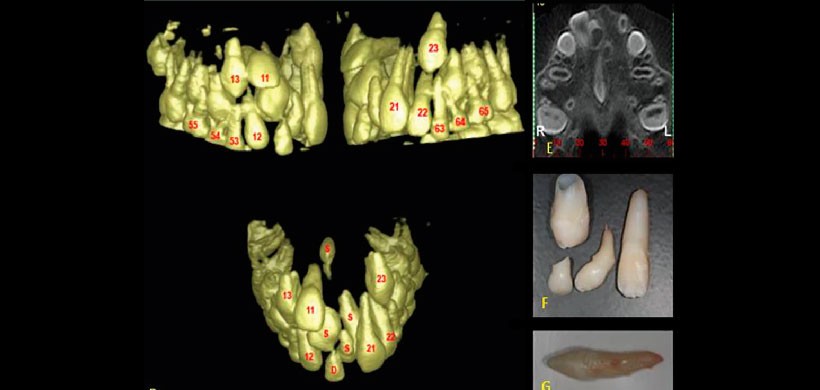

Fig 2. Renderizado 3 D, se muestra la presencia de un diente supernumerario localizada en el raffe medio a un nivel bien posterior. Nótese que pasa desapercibido en la radiografía panorámica

Fig 3. En la radiografía oclusal, panorámica y en los cortes tomográficos se aprecia la presencia de 2 dientes supernumerarios localizados a nivel medial del maxilar, ocasionando la impactación de las piezas 1.2, 1.1, 2.1, 2.2 y 2.3